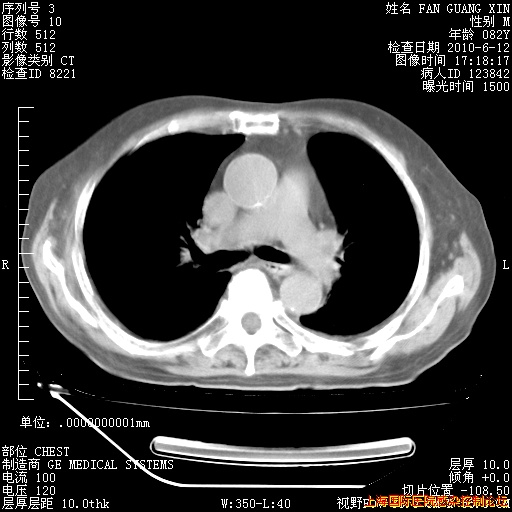

6月12日纵膈窗